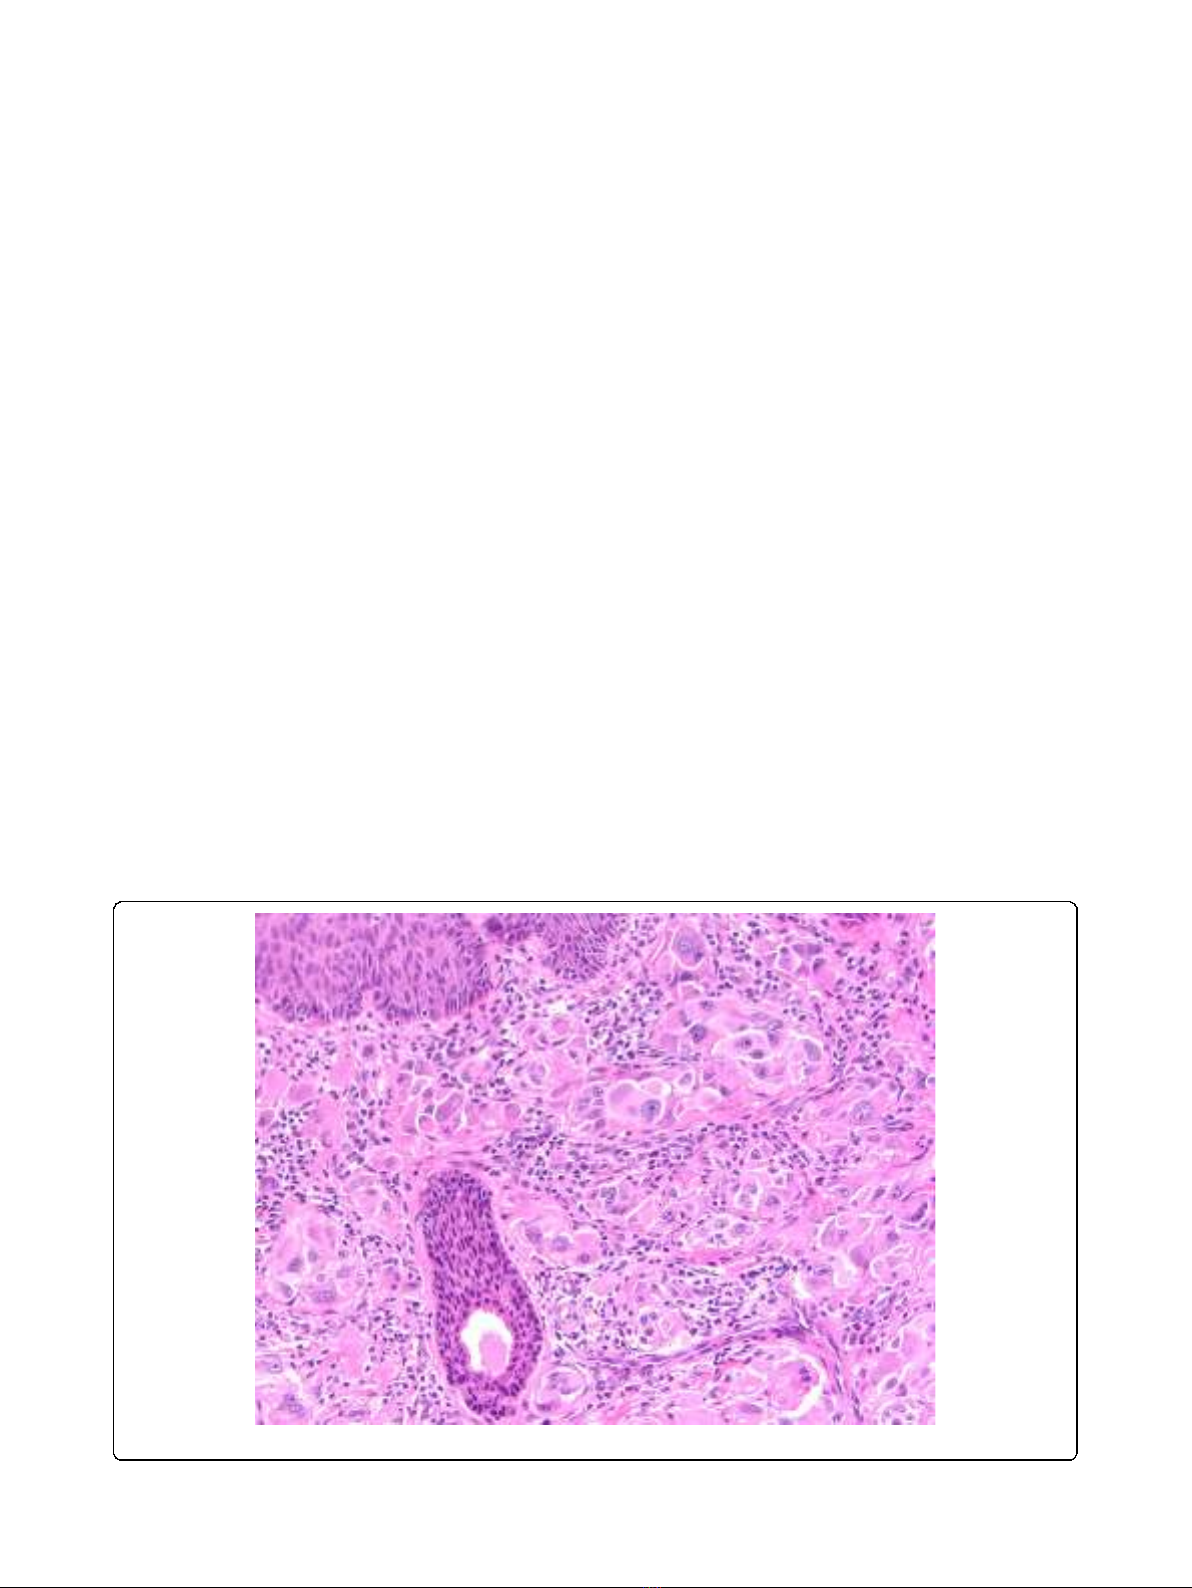

lymph node metastases. (Figure 1).

Figure 1 Atypical Spitz. Example of atypical Spitz neoplasm of uncertain biological significance.